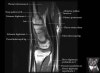

- Coronal section

Coronal T1 imaging evaluates bone marrow signal (ex. increased in avascular necrosis) and the relationship of the osseous structures to each other (ex. scapholunate disassociation).